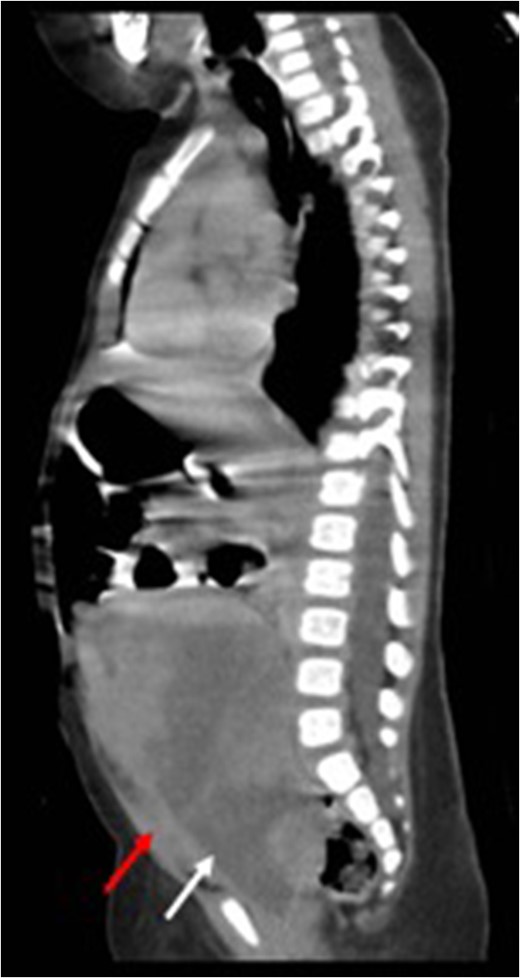

Sagittal view (CT) for the mass (white arrow) post-chemotherapy showing reduction in size (red arrow) bladder.